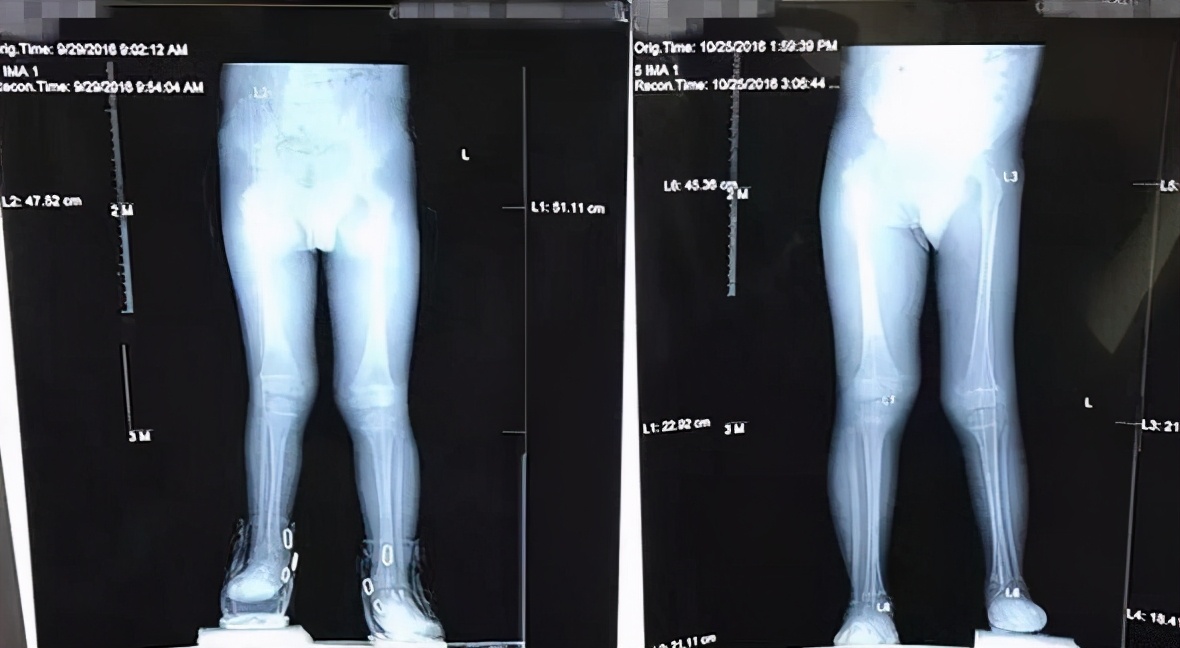

双下肢不等长的X光片

儿童双下肢不等长是小儿骨科常见的类型。原因有:外伤后骨骺异常发育、先天性双下肢发育异常、脊髓灰质炎后遗症、先天性髋关节发育异常等等。主要判断标准是影像学诊断中下肢骨骼出现绝对差值。